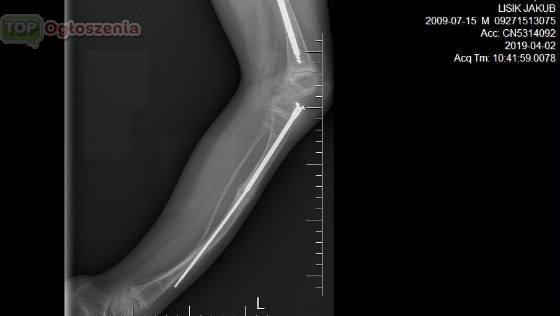

jest pacjentem Kliniki UDSK Białystok w

Której wszczepiono specjalny implant teleskopowy. Proteza rośnie wraz z dzieckiem i zapobiega ciągłemu łamaniu się kości. Operację przeprowadził Śp Wojciech Zalewski z Kliniki Ortopedii i Traumatologii Dziecięcej w Białymstoku . osteogenesis imperfecta, czyli wrodzona łamliwość kości.

Kubuś ma 9 lat . Od urodzenia jest pod opieką leczony farmakologlicznie ortopedycznie za sobą ma ponad 30 samoistnych złamań kości i kilka operacji przed Kuba następne zabiegi najbliższy 27 mają 2019 wyjazd do kliniki i wyznaczony zabieg wymiany implantu 29 maja 2019r przez dr Maciej Gerard Gendorff.

By zahamować postępy choroby przyjmują leki (bisfosfoniany) i wszczepia się im implanty do kości udowych i piszczelowych. Tel 511-417-140